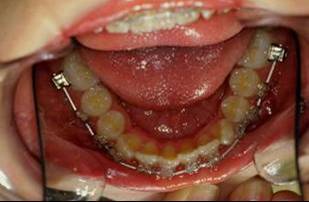

En fouillant dans mes cas j'ai trouve celui ci qui presente une beance assez importante. Je me suis rappele qu'un certain message etait lance il y a qq temps a propos d'un enfant qui presente une beance et de savoire comment faire dans ce cas. Je pense qu'il est interessant de voir comment les uns et les autres prennent en charge ce type de cas. Il s'agit d'un fille de 12 ans, succion de pouce, interposition linguale totale, beance de molaire a molaire, respiration mixte, incompetence labiale au repos, fonction labiale serree. Le total quoi!!! Voici la premiere serie de photos

la suite de documents, comme vous allez le voir le premier moyen est un qh, mais quelle sera la suite?

1- RDV 1: QH

2- RDV 2 : Commencer avec ecran buccal + exercice de respiration

3- Quant elle est capable de garder oral screen toute la nuit je considere que la batail est gagnee

4- Collage de l'arcade sup, presque 6 mois apres et voici le photo apres seance de college